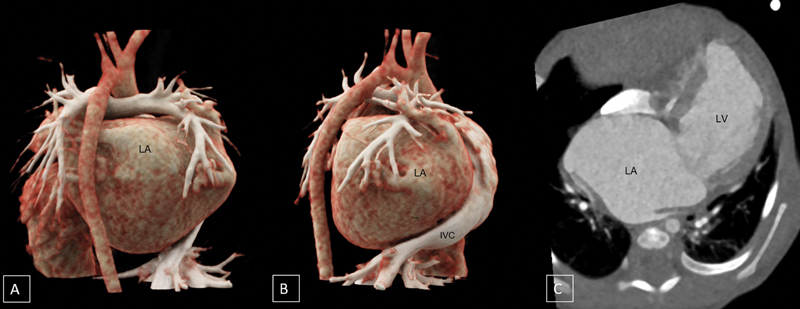

摘要左冠状动脉异常起源于肺动脉是一种罕见的先天性异常,伴有冠状动脉偷取和心肌缺血。左心室扩张导致二尖瓣反流导致左房增大。我们报告一个罕见的病例巨大左心房的婴儿与alcapa介导的继发性二尖瓣反流,这是迄今为止尚未报道。

Anomalous origin of the left coronary artery (ALCAPA) from the pulmonary artery is a rare congenital anomaly with coronary steal and myocardial ischemia. The left ventricular dilatation leads to mitral regurgitation causing left atrial enlargement. We report a rare case of giant left atrium in an infant with ALCAPA-mediated secondary mitral regurgitation, which has been hitherto unreported.